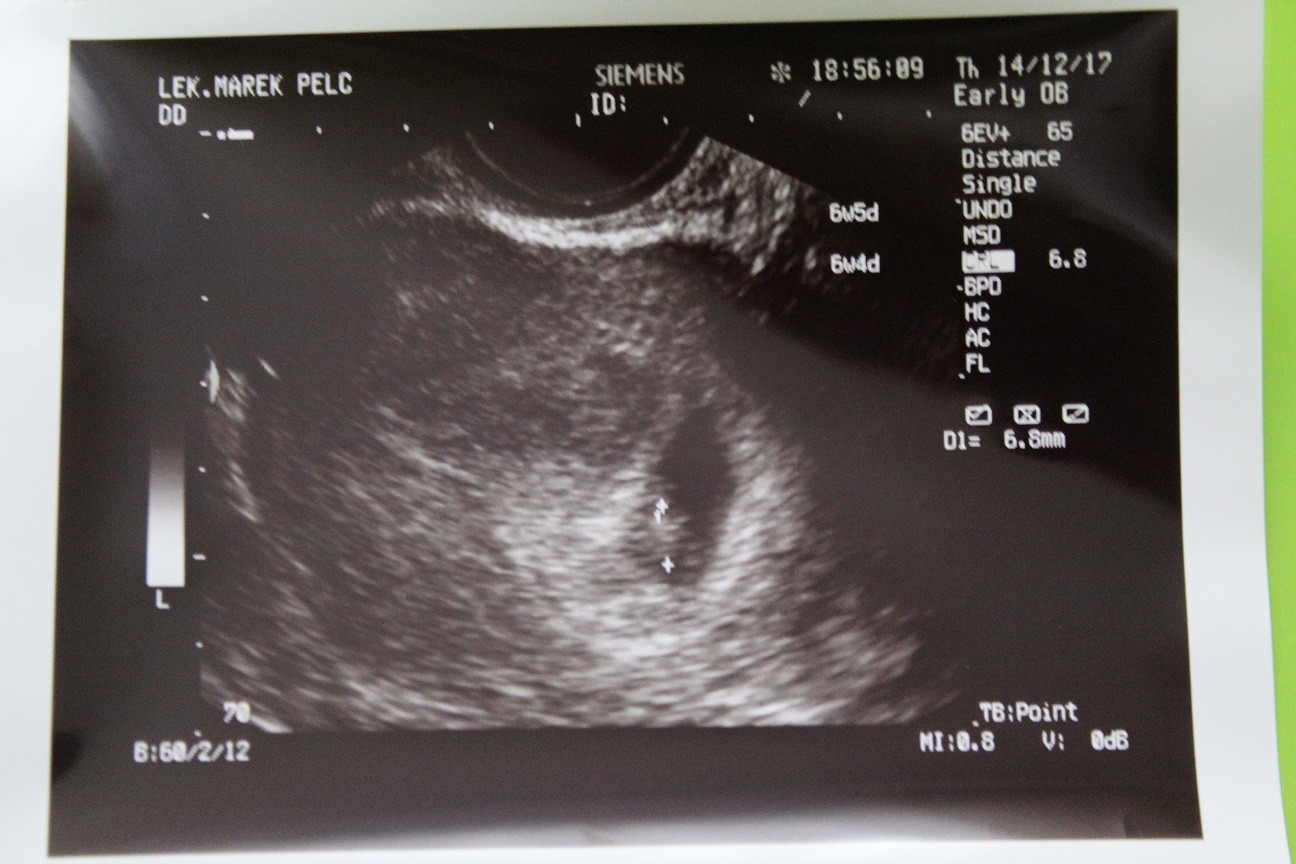

Wczorajsza wizyta super,mam juz kartę ciąży,termin na 4.08 ale rozwiązujemy się końcem lipca już mi powiedział.Dzidziuś ma 6,8mm,serducho pięknie bije,ciałko żółtkowe tez jest ok.Dostałam skierowanie na badania zapewne standardowo morfologia,hbs,tsh,toxo,cukier,hiv,hcv,grupa krwi i jeszcze jedno ale nie rozczytam

W badaniu ginekologicznym tez czysto.Następna wizyta 16.01

acha i wiek ciąży z usg pokrywa się z OM.